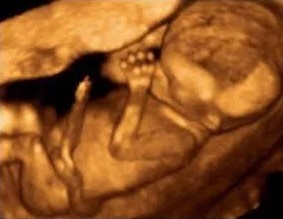

Der Mensch wird nicht als Augentier geboren. Ein Embryo kann lediglich hell und dunkel unterscheiden, das gilt noch kurz nach der Geburt noch für den Säugling. Erst mit dem zwölften Lebensmonat sind die wesentlichsten biologischen Elemente des visuellen Systems ausgebildet. Die Ausreifung der Fovea centralis - der Ort des schärfsten Sehens – dauert bis ins vierte Lebensjahr. Für die Kultur mag der Sehsinn der entscheidende sein, nicht aber für die Biologie des Menschen. In der Kinderziehung ist es ein anstrengender pädagogischer Prozess, die Lust des Kleinkindes, die Welt mit seinen taktilen Nah-Sinnen zu erkunden, zu brechen und den Primat des visuellen Distanz-Sinnes durchzusetzen.

Schon wenige Wochen nach Befruchtung der Eizelle reagiert der Embryo auf Berührungsreize auf der Oberfläche seines gespürten Leibes. Ab der siebten Schwangerschaftswoche reagieren die neun bis 16 Millimeter großen Embryos mit einem Zucken auf Berührungsreize an den Lippen und ziehen den Kopf zurück. Kein anderes Sinnessystem ist so früh aktiv.

Ab der zehnten Schwangerschaftswoche beginnt der Fötus mit Streckbewegungen und Eigenberührungen des Gesichts seinen eigenen Körper zu ertasten. Ab der zwölften Schwangerschaftswoche beginnt er einzelne Finger zu bewegen sowie die Hände zu öffnen und zu schließen. Ab der 15. Schwangerschaftswoche beginnt er, seinen Daumen in den Mund zu führen und den Saugreflex zu stimulieren.

Noch in der 17. Schwangerschaftswoche kann der dann 13 Zentimeter Fötus kann nichts hören, der Lebensraum ist dunkel, er verfügt über keine sensorischen Systeme für geschmackliche oder Geruchs-Wahrnehmungen. Körperlich stimulieren kann ihn nur sein Tastsinn – aber diese Stimulation ist notwendig, wenn sich ein sensorisches System entwickeln soll.